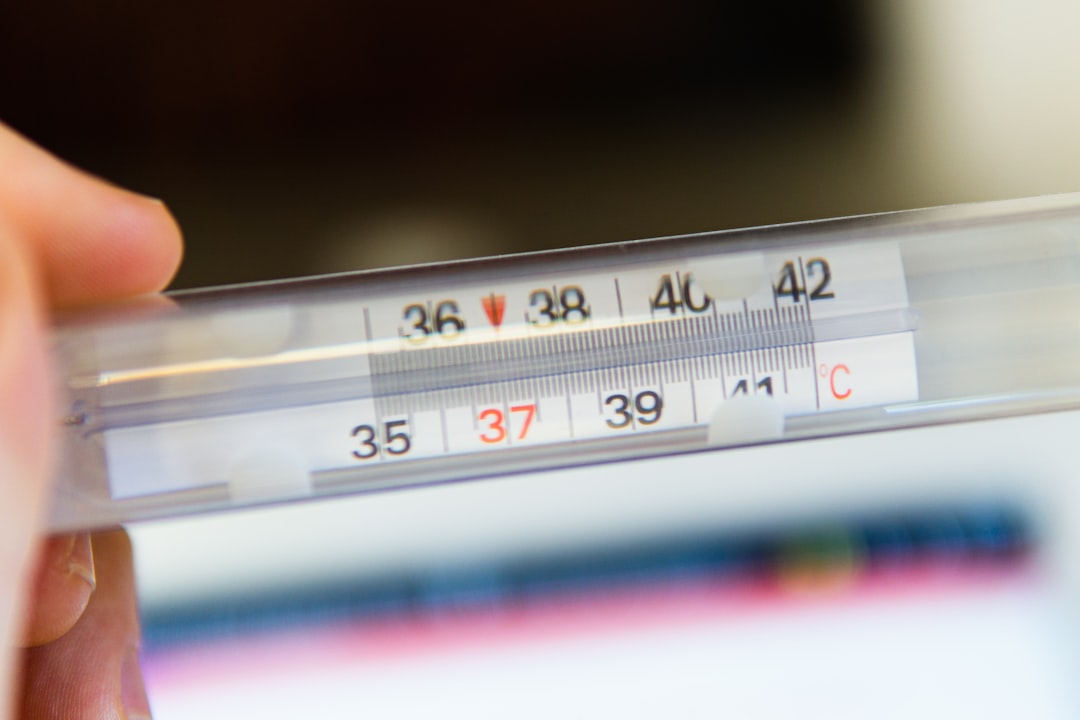

В Бурятию из Монголии привезли корь вместо сувениров

За два месяца в регионе зарегистрировали три случая заболевания